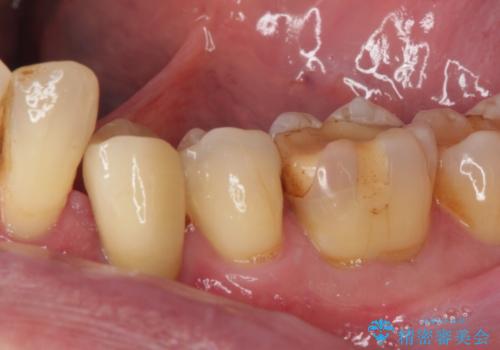

検査で見つかった虫歯 セラミッククラウンでの治療

担当医 岡田康成